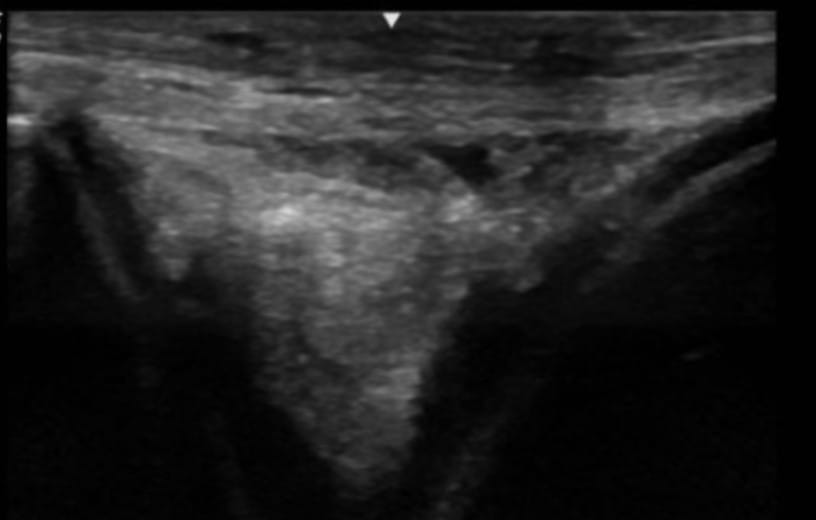

Ultrasound of the right stifle showed moderate medial femorotibial joint effusion with small hyperechoic particles, consistent with thin cartilage debris. There was a 1.5 cm x 0.5 cm defect in the abaxial portion of the medial trochlear ridge.

There was mild cranial meniscotibial ligament desmopathy. There was mild degenerative change in the axial portion of the medial meniscus. There was mild sonographic evidence of axial subchondral bone remodeling of the medial condyle at the level of the most weight-bearing portion. Ultrasound of the left stifle showed similar but less pronounced changes.